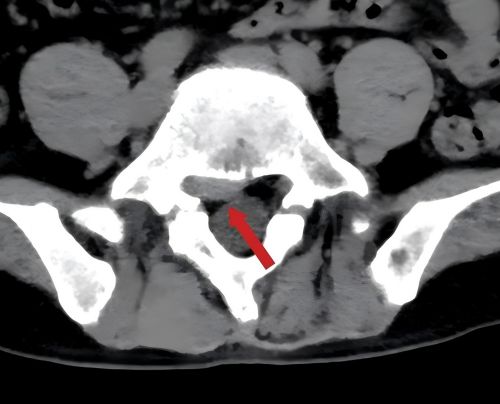

术前检查显示:患者腰5/骶1椎间盘突出,右侧神经根受压